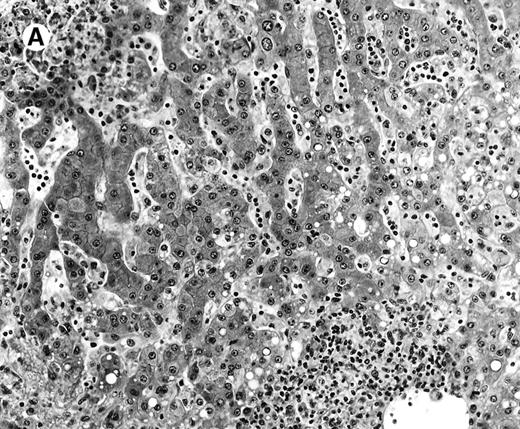

All cases showed essentially similar histologic findings in the liver and spleen. The splenic white pulp was inconspicuous to markedly depleted, whereas the sinusoids showed a prominent lymphoid infiltration (Figure 1A). There was striking hemophagocytosis within the splenic sinusoids (Figure 1B). The infiltrating lymphocytes were small and lacked significant cytologic atypia (Figure 1B). Immunoblasts and plasma cells were not prominent. The liver had prominent portal as well as sinusoidal infiltrates of small lymphocytes morphologically identical to those noted in the spleen (Figure 2). There was intracellular and intracanalicular cholestasis, steatosis, and focal necrosis. Hemophagocytosis was present within the sinusoids. In case 5, the spleen showed extensive areas of necrosis mainly in the perifollicular and periarteriolar lymphoid sheaths of the white pulp with the presence of immunoblasts reminiscent of IM.

Histologic findings in the liver.

(A) Liver specimen from case 1 shows prominent portal and sinusoidal lymphoid infiltrate (hematoxylin and eosin, × 200). (B) The infiltrating lymphocytes are small and lack cytologic atypia (hematoxylin and eosin, × 600).